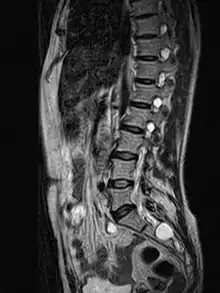

| MRI image showing a Tarlov cyst | |

Tarlov cysts, are type II innervated meningeal cysts, cerebrospinal-fluid-filled (CSF) sacs most frequently located in the spinal canal of the sacral region of the spinal cord (S1–S5) and much less often in the cervical, thoracic or lumbar spine. They can be distinguished from other meningeal cysts by their nerve-fiber-filled walls. Tarlov cysts are defined as cysts formed within the nerve-root sheath at the dorsal root ganglion.[2] The etiology of these cysts is not well understood; some current theories explaining this phenomenon have not yet been tested or challenged but include increased pressure in CSF, filling of congenital cysts with one-way valves, inflammation in response to trauma and disease. They are named for American neurosurgeon Isadore Tarlov, who described them in 1938.[3]

Tarlov cysts are relatively uncommon when compared to other neurological cysts. Initially, Isadore Tarlov believed them to be asymptomatic, however as his research progressed, Tarlov found them to be symptomatic in a number of patients. These cysts are often detected incidentally during MRI or CT scans for other medical conditions. They are also observed using magnetic resonance neurography with communicating subarachnoid cysts of the spinal meninges. Cysts with diameters of 1 cm or larger are more likely to be symptomatic; although cysts of any size may be symptomatic dependent on location and etiology. Some 40% of patients with symptomatic Tarlov cysts can associate a history of trauma or childbirth.[4] Current treatment options include CSF aspiration, fibrin-glue therapy, laminectomy with wrapping of the cyst, among other surgical treatment approaches. Interventional treatment of Tarlov cysts is the only means by which symptoms might permanently be resolved due to the fact that the cysts often refill after aspiration. Tarlov cysts often enlarge over time, especially if the sac has a check valve type opening. They are differentiated from other meningeal and arachnoid cysts because they are innervated and diagnosis can in cases be demonstrated with subarachnoid communication.

MRI, or Magnetic Resonance Imaging, is considered the imaging study of choice in identifying Tarlov cysts. MRI provides better resolution of tissue density, absence of bone interference, multiplanar capabilities, and is noninvasive. Plain films may show bony erosion of the spinal canal or of the sacral foramina. On MRI pictures, the signal is the same as the CSF one.